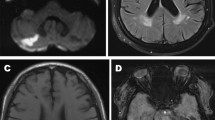

MR images were analyzed using qualitative assessment of the MRI features of SVD (Fig. 1) according to the STRIVE standards [1] by two experienced neuroradiologists (K.E.I. and A.B.M.); in case of interrater discreepancy, the data were discussed with the third neuroradiologist (K.M.V.). The analysis was performed using the eFilm Workstation 4.2.2 (IBM Watson Health, United States).

WMH was detected on T1 and FLAIR images; for the entire brain, the grade was indicated on the modified Fazekas (F) scale (F0, absence; F1, single lesions; F2, single and partially lesions; F3, confluent lesions/leukoaraiosis) [12] (Fig. 1).